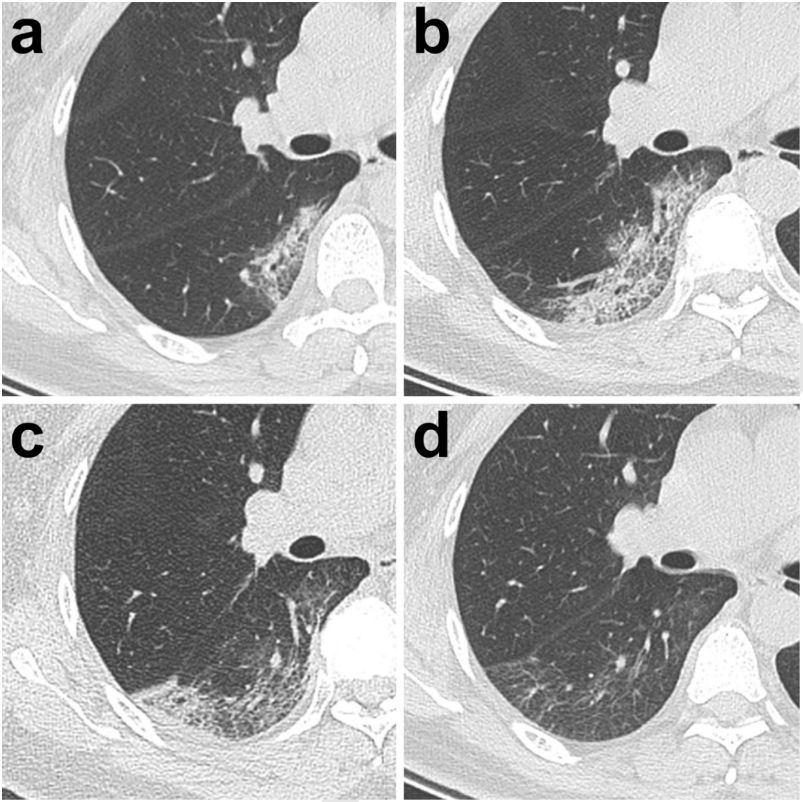

在武漢協(xié)和醫(yī)生們的建議下,飛利浦科學家與兄弟團隊針對新冠肺炎的CT影像學特點及臨床需求,整合IntelliSpace Portal后處理工作站中COPD(慢阻肺分析)、LNA(肺結節(jié)分析)、Liver(肝臟分析)、MMTT(多平臺多時間追蹤分析)等多個模塊的功能,在面對數(shù)萬病人數(shù)據(jù)時,為醫(yī)生們全面評估與追蹤病人影像表現(xiàn)提供了一個可行的預案,讓醫(yī)生們從繁重的閱片工作中解脫出來、將更多的精力投入到對疾病本身的研究以及對病人的關懷。(下圖是由武漢協(xié)和醫(yī)院提供的典型病例)

【1】 Pan Feng, Ye Tianhe, …, Zheng Chuansheng. Time course of lung changes on chest CT during recovery from 2019 Novel Coronavirus (COVID-19) pneumonia. DOI: 10.1148/radiol.2020200370